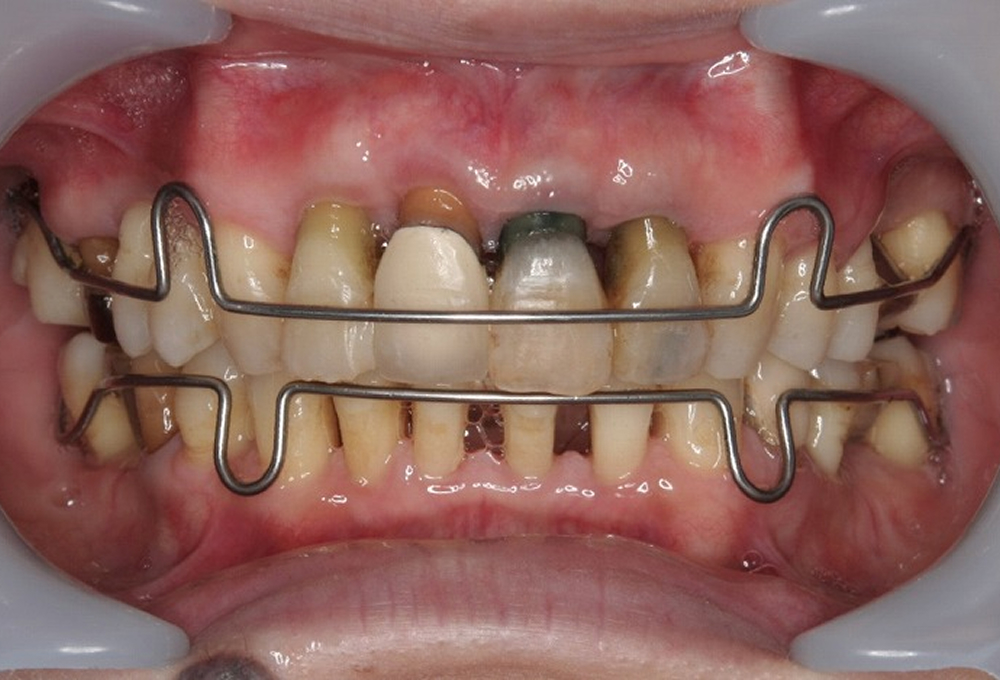

⑥矯正中